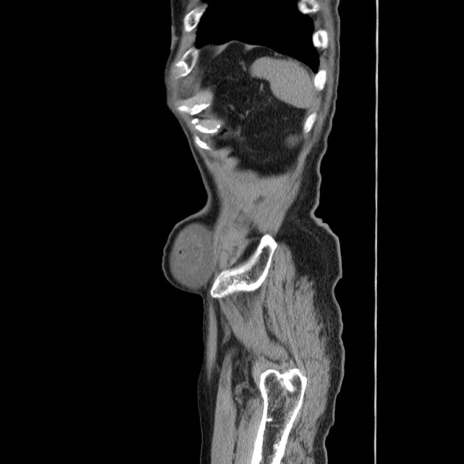

症例24(矢状断像)

【症例】80歳代男性

【主訴】左側腹部痛、嘔吐

【現病歴】本日早朝より左腹部に痛みあり。昼頃嘔吐認めたため、救急要請。

【既往歴】直腸癌(Mile手術)、胆摘

【身体所見】意識清明、BT 35.9℃、BP 221/93mmHg、SpO2 97%(RA) 、腹部:左ストーマ周囲に限局性の腹部膨隆あり。 膨隆部自発痛・圧痛あり・軟。

【データ】WBC 7700、CRP 0.09